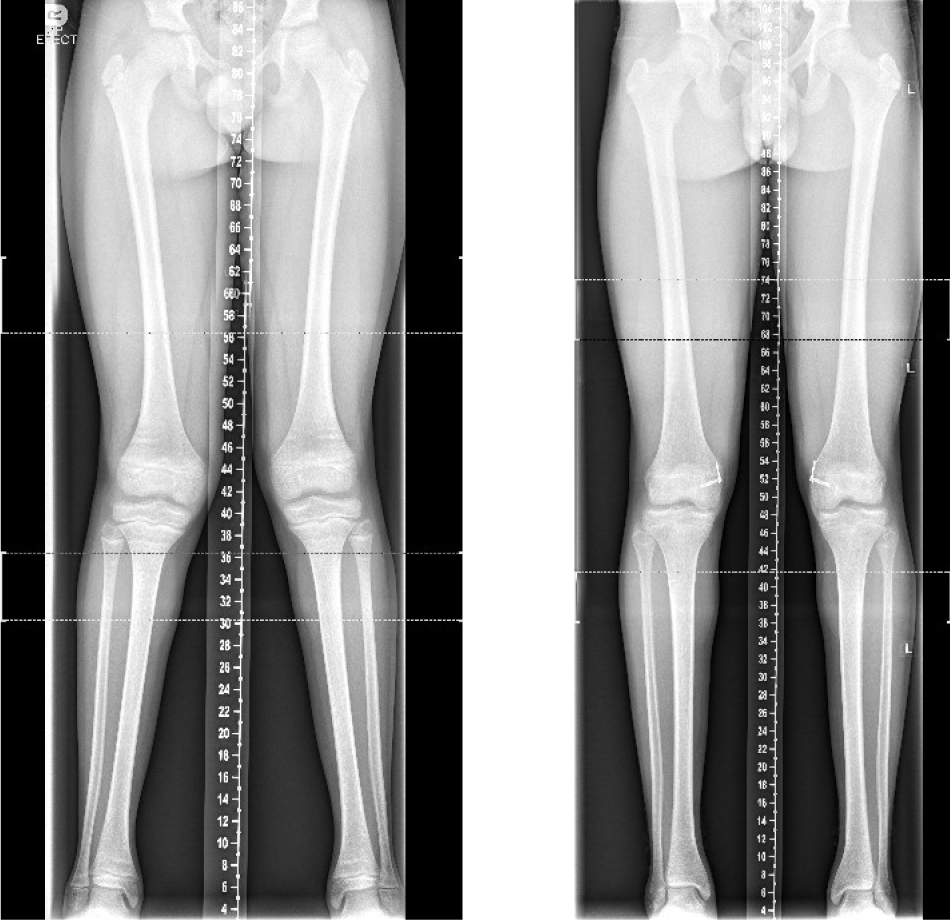

This surgery is often performed when one leg is shorter than the other, to stop the growth of the longer leg, allowing the other leg to catch up over time and ‘even up’ the legs. Epiphysiodesis may also be used to correct an angular deformity of the leg; for example, knock knees. The timing of each procedure is crucial and is calculated to allow the shorter leg to catch up by the time your child’s growth stops.

Your child will be seen regularly in the clinic to check leg length difference or the bend in the legs with x-rays. If eight-plates or screws have been used and your child is still growing, they will need to have another operation to remove them under a general anaesthetic. If an x-ray shows that there is no more growth left, then the plates can remain in.